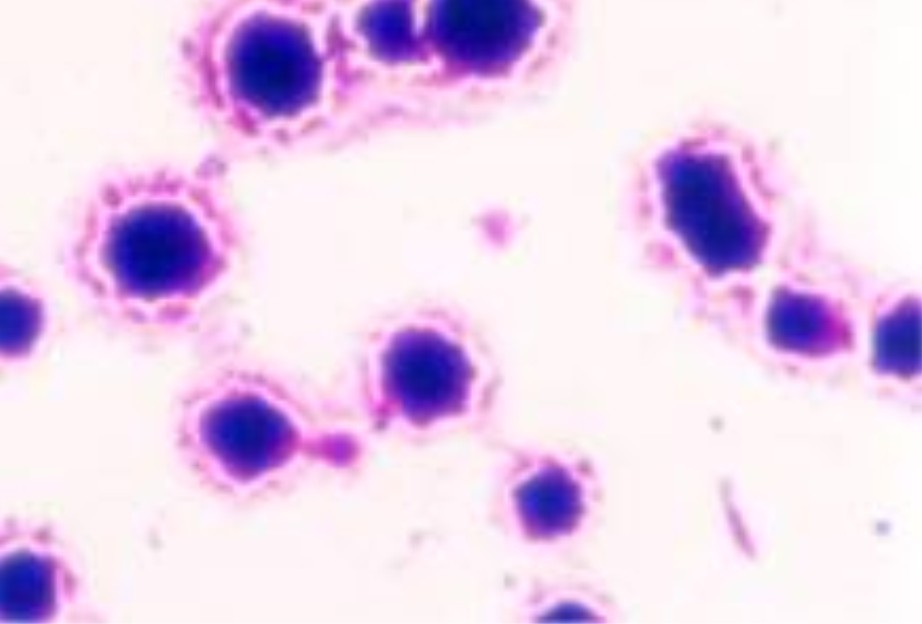

莫氏立克次体镜下图

立克次氏体